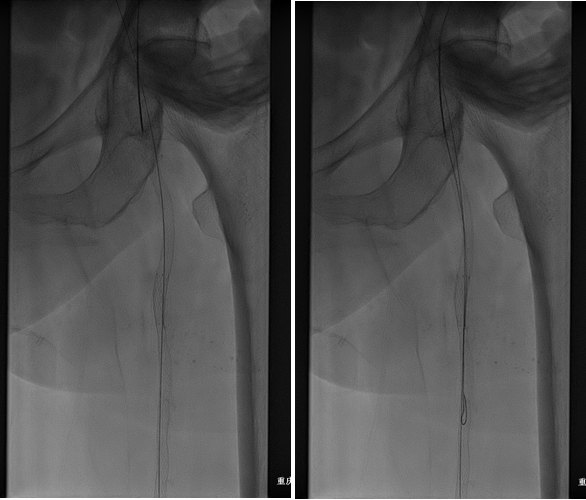

图:术中CT

图:术后效果